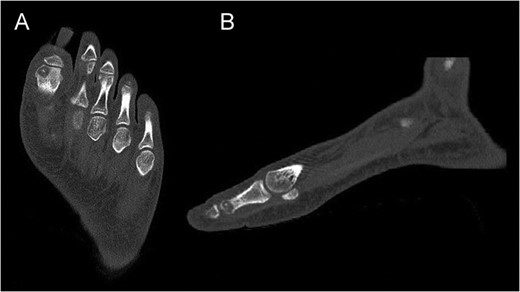

CT of the proximal phalanx of the left hallux: axial (A) and sagittal view (B), showing the recurrence of the OO and its extension to the articular surface.